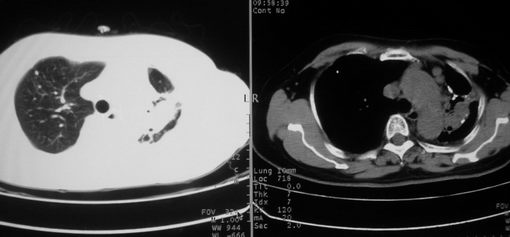

以下是引用李衡钧在2008-7-24 14:24:00的发言:[br]左侧胸廓变小,左肺上叶见大面积致密阴影,其内有空洞及不规则钙化。上纵隔略向左移位,上肺胸膜增厚。左肺门及纵隔淋巴结增大。右肺见散在的致密结节影。[br]印象:继发性肺结核。